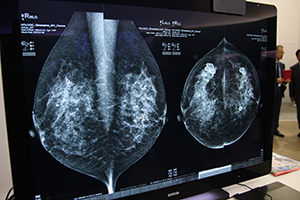

このほか,コンピュータ診断支援装置「Cenova」のソフトウェアとして,2D画像上で石灰化と腫瘤の場所を表示する“ImageChecker 9.3”や,乳腺密度を計測する乳腺濃度ソフトウェア“Quantra”などを来場者にアピールした。

石灰化や腫瘤の場所を自動表示する |